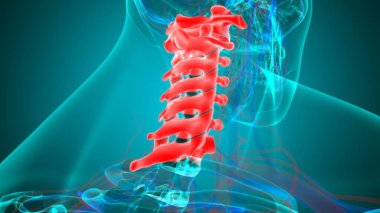

İnsan İskeleti Omurgası Servikal Omurga Anatomisi 3D İllüstrasyon